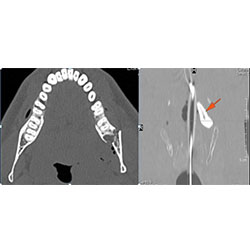

Mandible and Temporomandibular Joints

Dentition